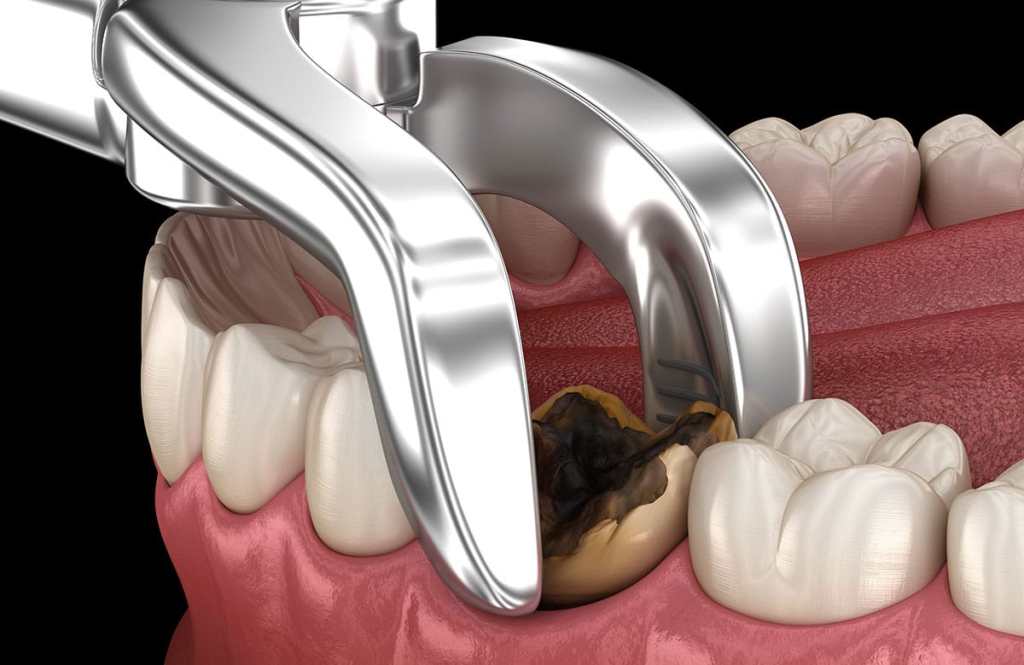

The main thing that acid reflux does is to wear away the enamel of your teeth. This is something that can easily be noticed by a compliant dentist and is a big reason to go and see your dentist regularly. But tooth erosion is permanent and is something that simply does not come back. This is pretty easy to discover and can feel like it is actually a problem with other things as well. But if your teeth are very sensitive then it could be a problem. One area that they could be sensitive or it could feel pain is when you are drinking hot or cold liquids. That can really show on the pain levels when your teeth are suffering from erosion.